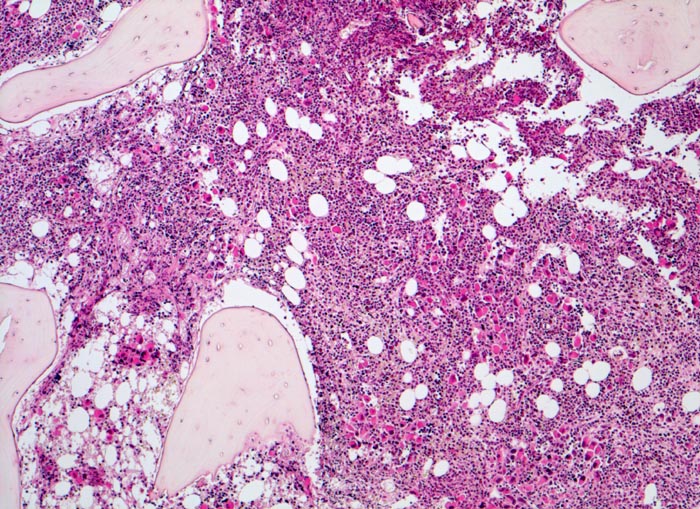

Primäre Myelofibrose (PMF)

Knochenmark, Beckenkamm

Hyperplastisches Mark mit wechselnder Verdrängung des Fettmarks. Schon in der Übersicht sind grössere Gruppen von Megakaryozyten erkennbar.

Splenomegalie, leichte Anämie, Leukozytose und Thrombozytose festgestellt bei einer Routineuntersuchung bei asymptomatischer Patientin.